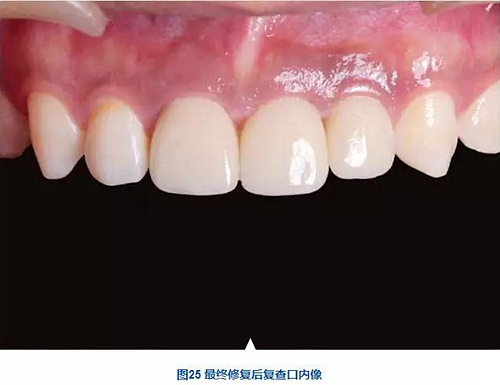

術(shù)后7個月,戴入最終修復(fù)體,紅白美學(xué)效果滿意。

種植體周圍骨水平穩(wěn)定,齦乳頭及齦高點位置穩(wěn)定,齦緣曲線形態(tài)理想,唇側(cè)軟硬輪廓良好,功能滿意,修復(fù)效果符合預(yù)期。

本病例在觀察期內(nèi),種植修復(fù)獲得了良好的軟硬組織美學(xué)效果和穩(wěn)定性。患者對治療效果滿意。